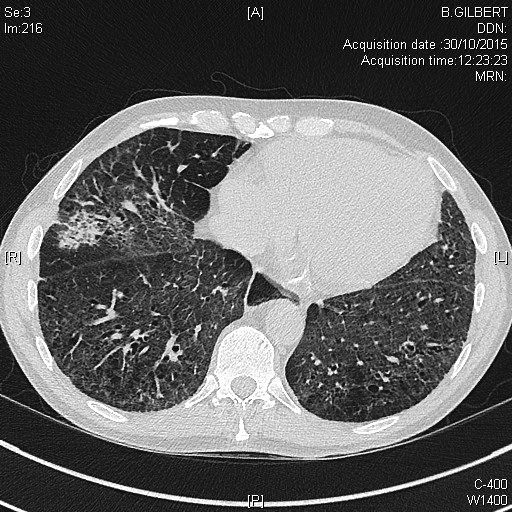

Nodules plumonaires excavés dans le cadre d'une granulomatose avec polyangéite